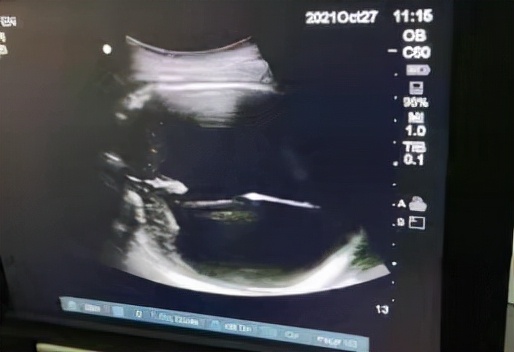

為確保手術萬無一失,術前醫護人員做足了“功課”。10月27日,手術正式開始,產科副主任醫師賴華、住院醫師祝慧婷,超聲科醫師、手術室護士齊聚上陣,為手術護航。超聲引導下抽出腦脊液680ml。術畢,彩超檢查提示胎兒雙頂徑為86mm,相較之前胎兒的雙頂徑及頭圍明顯縮小了,這為孕婦陰道分娩創造了良好的條件。術後,給予該孕婦預防抗炎治療,最終透過引產,該孕婦順利陰道分娩。